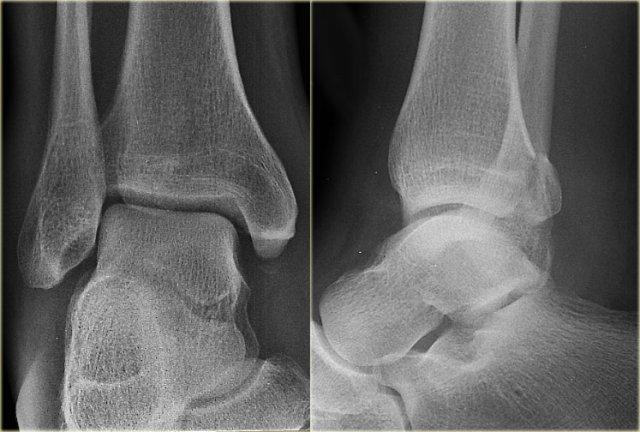

- Ấn tượng ban đầu

Các phim chụp X-quang cho thấy gãy mắt cá sau.

Nếu bạn chỉ mô tả đơn thuần là – gãy mắt cá sau – thì bạn đã bỏ sót vấn đề chính.

Đây có thể là gãy xương cổ chân không vững.

Gãy mắt cá sau đơn thuần là một phát hiện rất hiếm gặp.

- Nhìn vào hệ thống phân loại

Khi chúng ta xem xét sơ đồ, chúng ta sẽ nhận thấy rằng gãy mắt cá sau trong hầu hết các trường hợp là một phần của gãy Weber B hoặc Weber C.

Gãy xương thứ ba (tertius) thuộc Weber B giai đoạn 3

hoặc – do Weber C giai đoạn 4 (mũi tên).

Chúng ta cần xem lại phim để tìm các dấu hiệu bổ sung.

Vì bây giờ chúng ta đã biết cần tìm ở đâu, việc phát hiện các dấu hiệu bổ sung sẽ dễ dàng hơn.